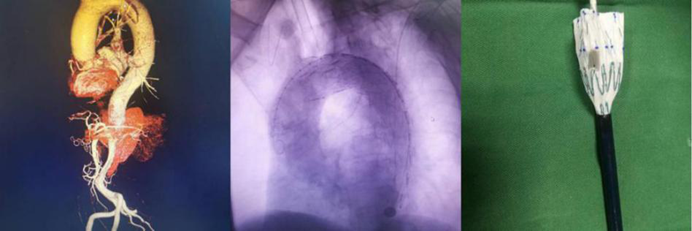

血管疾病專(zhuan) 業(ye) 組:常規開展主動脈夾層的腔內(nei) 手術、胸主動脈瘤、腹主動脈瘤的腔內(nei) 手術和開放手術、頸動脈內(nei) 膜剝脫和支架置入手術、肝硬化、門靜脈高壓症斷流、脾腎靜脈及門腔靜脈分流、下肢動脈閉塞症、深靜脈血栓形成、糖尿病足、血栓閉塞性脈管炎、動脈栓塞等疾病的外科血管旁路搭橋,血管成型,靜脈動脈化,球囊導管取栓,腔靜脈濾器植入,腸係膜靜脈血栓形成經股動脈穿刺腸係膜上動脈持續溶栓治療,大、小隱靜脈曲張微創手術,下腔靜脈、股動脈等血管損傷(shang) 的救治。並成功開展目前最前沿的高難度主動脈弓三開窗腹膜分支支架置入術。

胸主動脈開窗、覆膜支架置入術